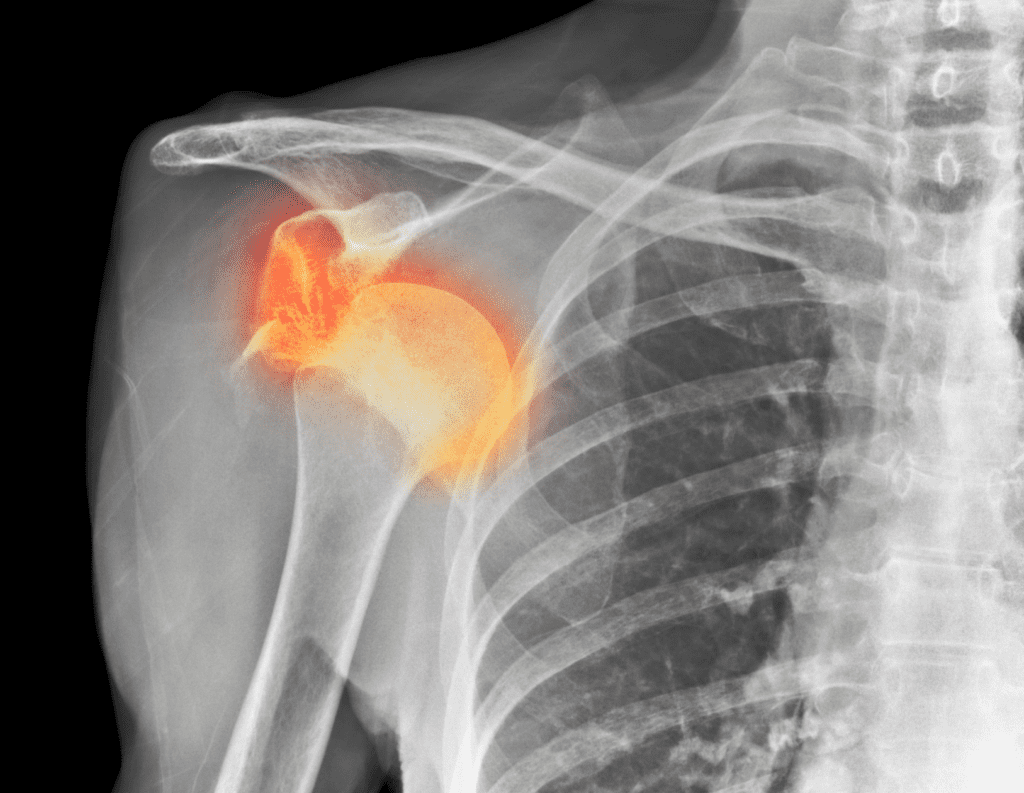

Impingement means something is getting pinched. In the shoulder, it’s usually the tendons of your rotator cuff or a bursa getting compressed under the bony arch of your shoulder blade (acromion). But the critical question, why is there excessive compression?

- True Mechanical Pinch: The space itself is physically narrowed.